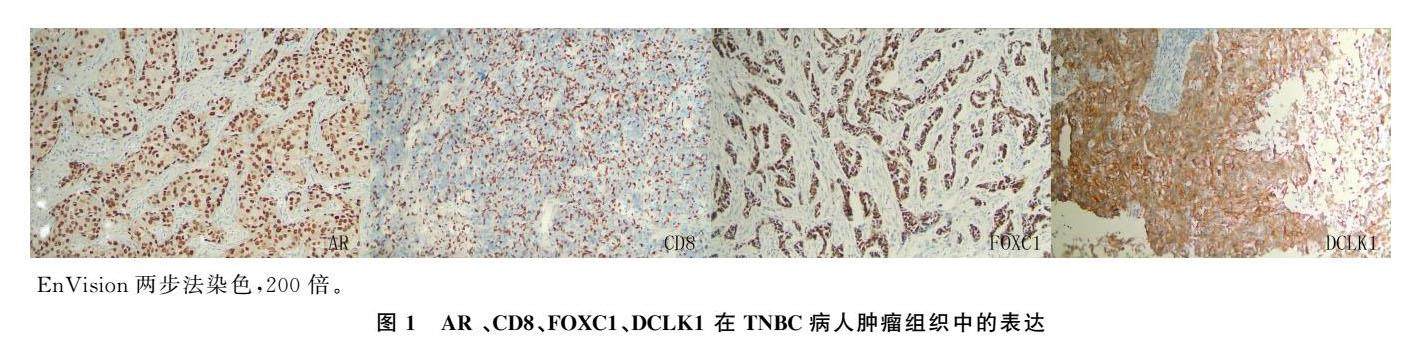

论著 | 基于免疫组化结果的三阴性乳癌分子分型及预后分析

论著 | 基于免疫组化结果的三阴性乳癌分子分型及预后分析